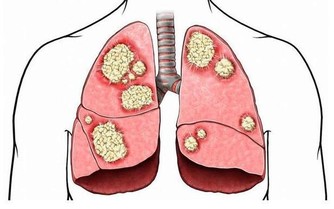

8. 吃得太少也會導致器官衰竭和心臟問題

除了根本不吃東西的人之外,有些人吃的食物數量很少,幾乎不會對身體產生任何有價值的影響,

比如神經性厭食症患者,它們的身體正在經歷幾乎完全的飢餓。

其後果可能與完全挨餓一樣糟糕。

最終,心肌梗塞或心髒病發作和器官衰竭是他們典型的死亡原因。